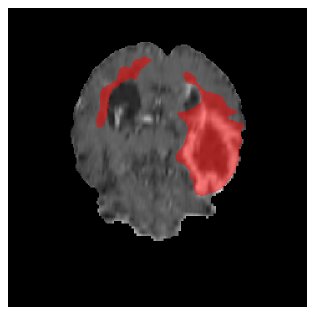

Appendix A Qualitative results

Figure 5 illustrates the segmentation evolution for the same BRATS patient in S2 sequence. The key difference here is that the best buffer-free strategy is EWC (=1), and training on BRATS data starts from episode 2 instead of episode 1 as BRATS is encountered at episode 2 in S2. The cumulative approach retains segmentation across episodes but continues to generate false positives, which become even more pronounced in the final episode. The naive approach, lacking a CL mechanisms, completely overrides previous knowledge, leading to failed segmentation in later episodes. EWC (=1) approach initially maintains segmentation but experiences a sharp decline in episode 4, where it fails to segment the tumor. In the final episode, it undersegments the lesion, missing a significant portion of the tumor. In contrast, the proposed approach consistently preserves segmentation across episodes. While initially introducing false positives, it gradually refines predictions, retaining the tumor region while minimizing misclassifications. It maintains clear tumor delineation by the final episode, demonstrating effective knowledge retention and adaptability throughout training.